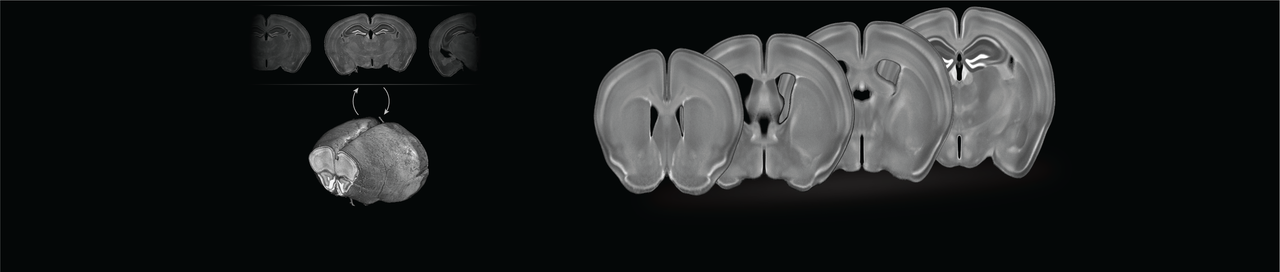

In this study, we sought to allow for template-based segmentation of 2-dimensional mouse brain slices acquired with fluorescence microscopy. Typically, a stain called DAPI is used to show the brain structures, and up to three additional channels are used for measuring the molecule(s) of interest. So, we needed to construct a population-based template of the mouse brain from slices stained with DAPI.

We collected consecutive coronal slices from 12 mice (C57BL/6) covering the majority of the cerebrum and DAPI-stained them. With the help of Allen Mouse Brain Common Coordinate Framework (CCFv3) we were able to reconstruct all 12 brains. This was done by iteratively stacking the 2-dimensional slices into 3-dimensional volumes, registering, and slicing. With the reconstructed brains, we could perform the template creation in 3-dimensional space. Using this new template in combination with the CCFv3 we started over with the reconstruction and template creation resulting in the final well-defined DAPI template (shown in the beginning of the post).

We were thrilled with how well the reconstruction process worked and happy to see a well-defined and smooth template. New coronal slices were easily registered to the template, so we wrote a small python program for automatic template-based segmentation (see the full paper for examples). To encourage the scientific community to utilize and improve the template, we have made all the data available in a well-structured and ordered fashion here: https://doi.org/10.12751/g-node.16wrxa